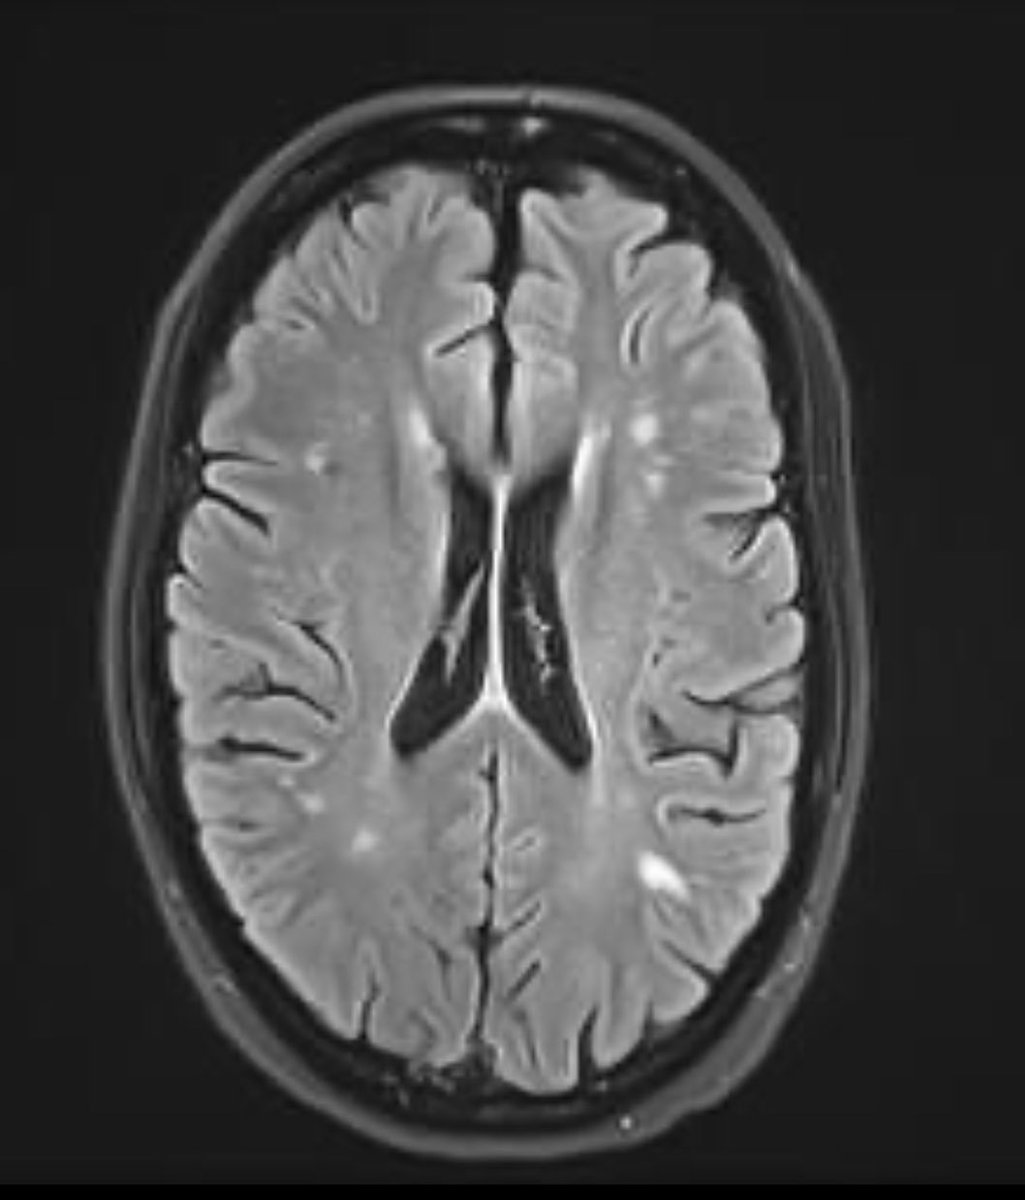

When I became ill with #LongCovid, I left practice for a bit. Took a job as a medical writer as I rehabilitated. Now, I come across articles I wrote last year that I don’t have any memory of writing. This virus can demolish the brain. Yet- we’re ok with pilots getting it now.

@danaparish I can’t express to you how terrifying it was to experience the brain injury and not understand what was happening to me. I started a FB group in Sept 2020 just for people with COVID brain damage just to convince myself I wasn’t alone. Turns out… I wasn’t. Even way back then.

Life with #LongCovid:. Today I’m seeing a concussion specialist. One who sees guys in the NFL. And I never got hit in the head. But have symptoms similar to traumatic brain injury victims. Three years after infection. Wear a mask.

Brain scan ordered for post COVID inflammation denied by PPO insurance because it’s “considered investigational, without adequate trial data to support its use.” . Anyone have #LongCovid “trial data” I can borrow? . 🤦🏼♀️.

The “let everyone get it” plan only works if we have the resources in place to manage the aftermath. We don’t. Mild COVID can lead to the serious brain injury seen in #LongCovid. To not anticipate this neurological devastation will be one of the worst errors of the pandemic.